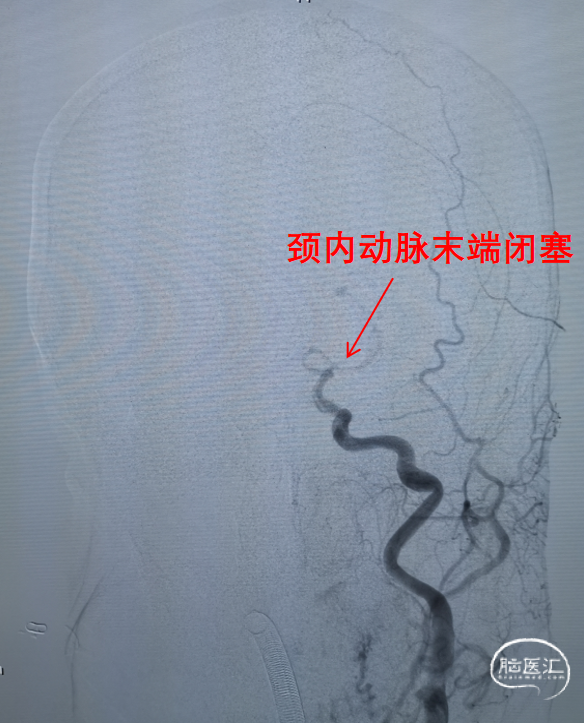

左侧颈动脉造影提示左侧颈内动脉末端闭塞。

- 头颅CT未见出血,头颅CTA提示左侧颈内动脉末端闭塞,发病时间6小时内可不行头颅CTP检查;